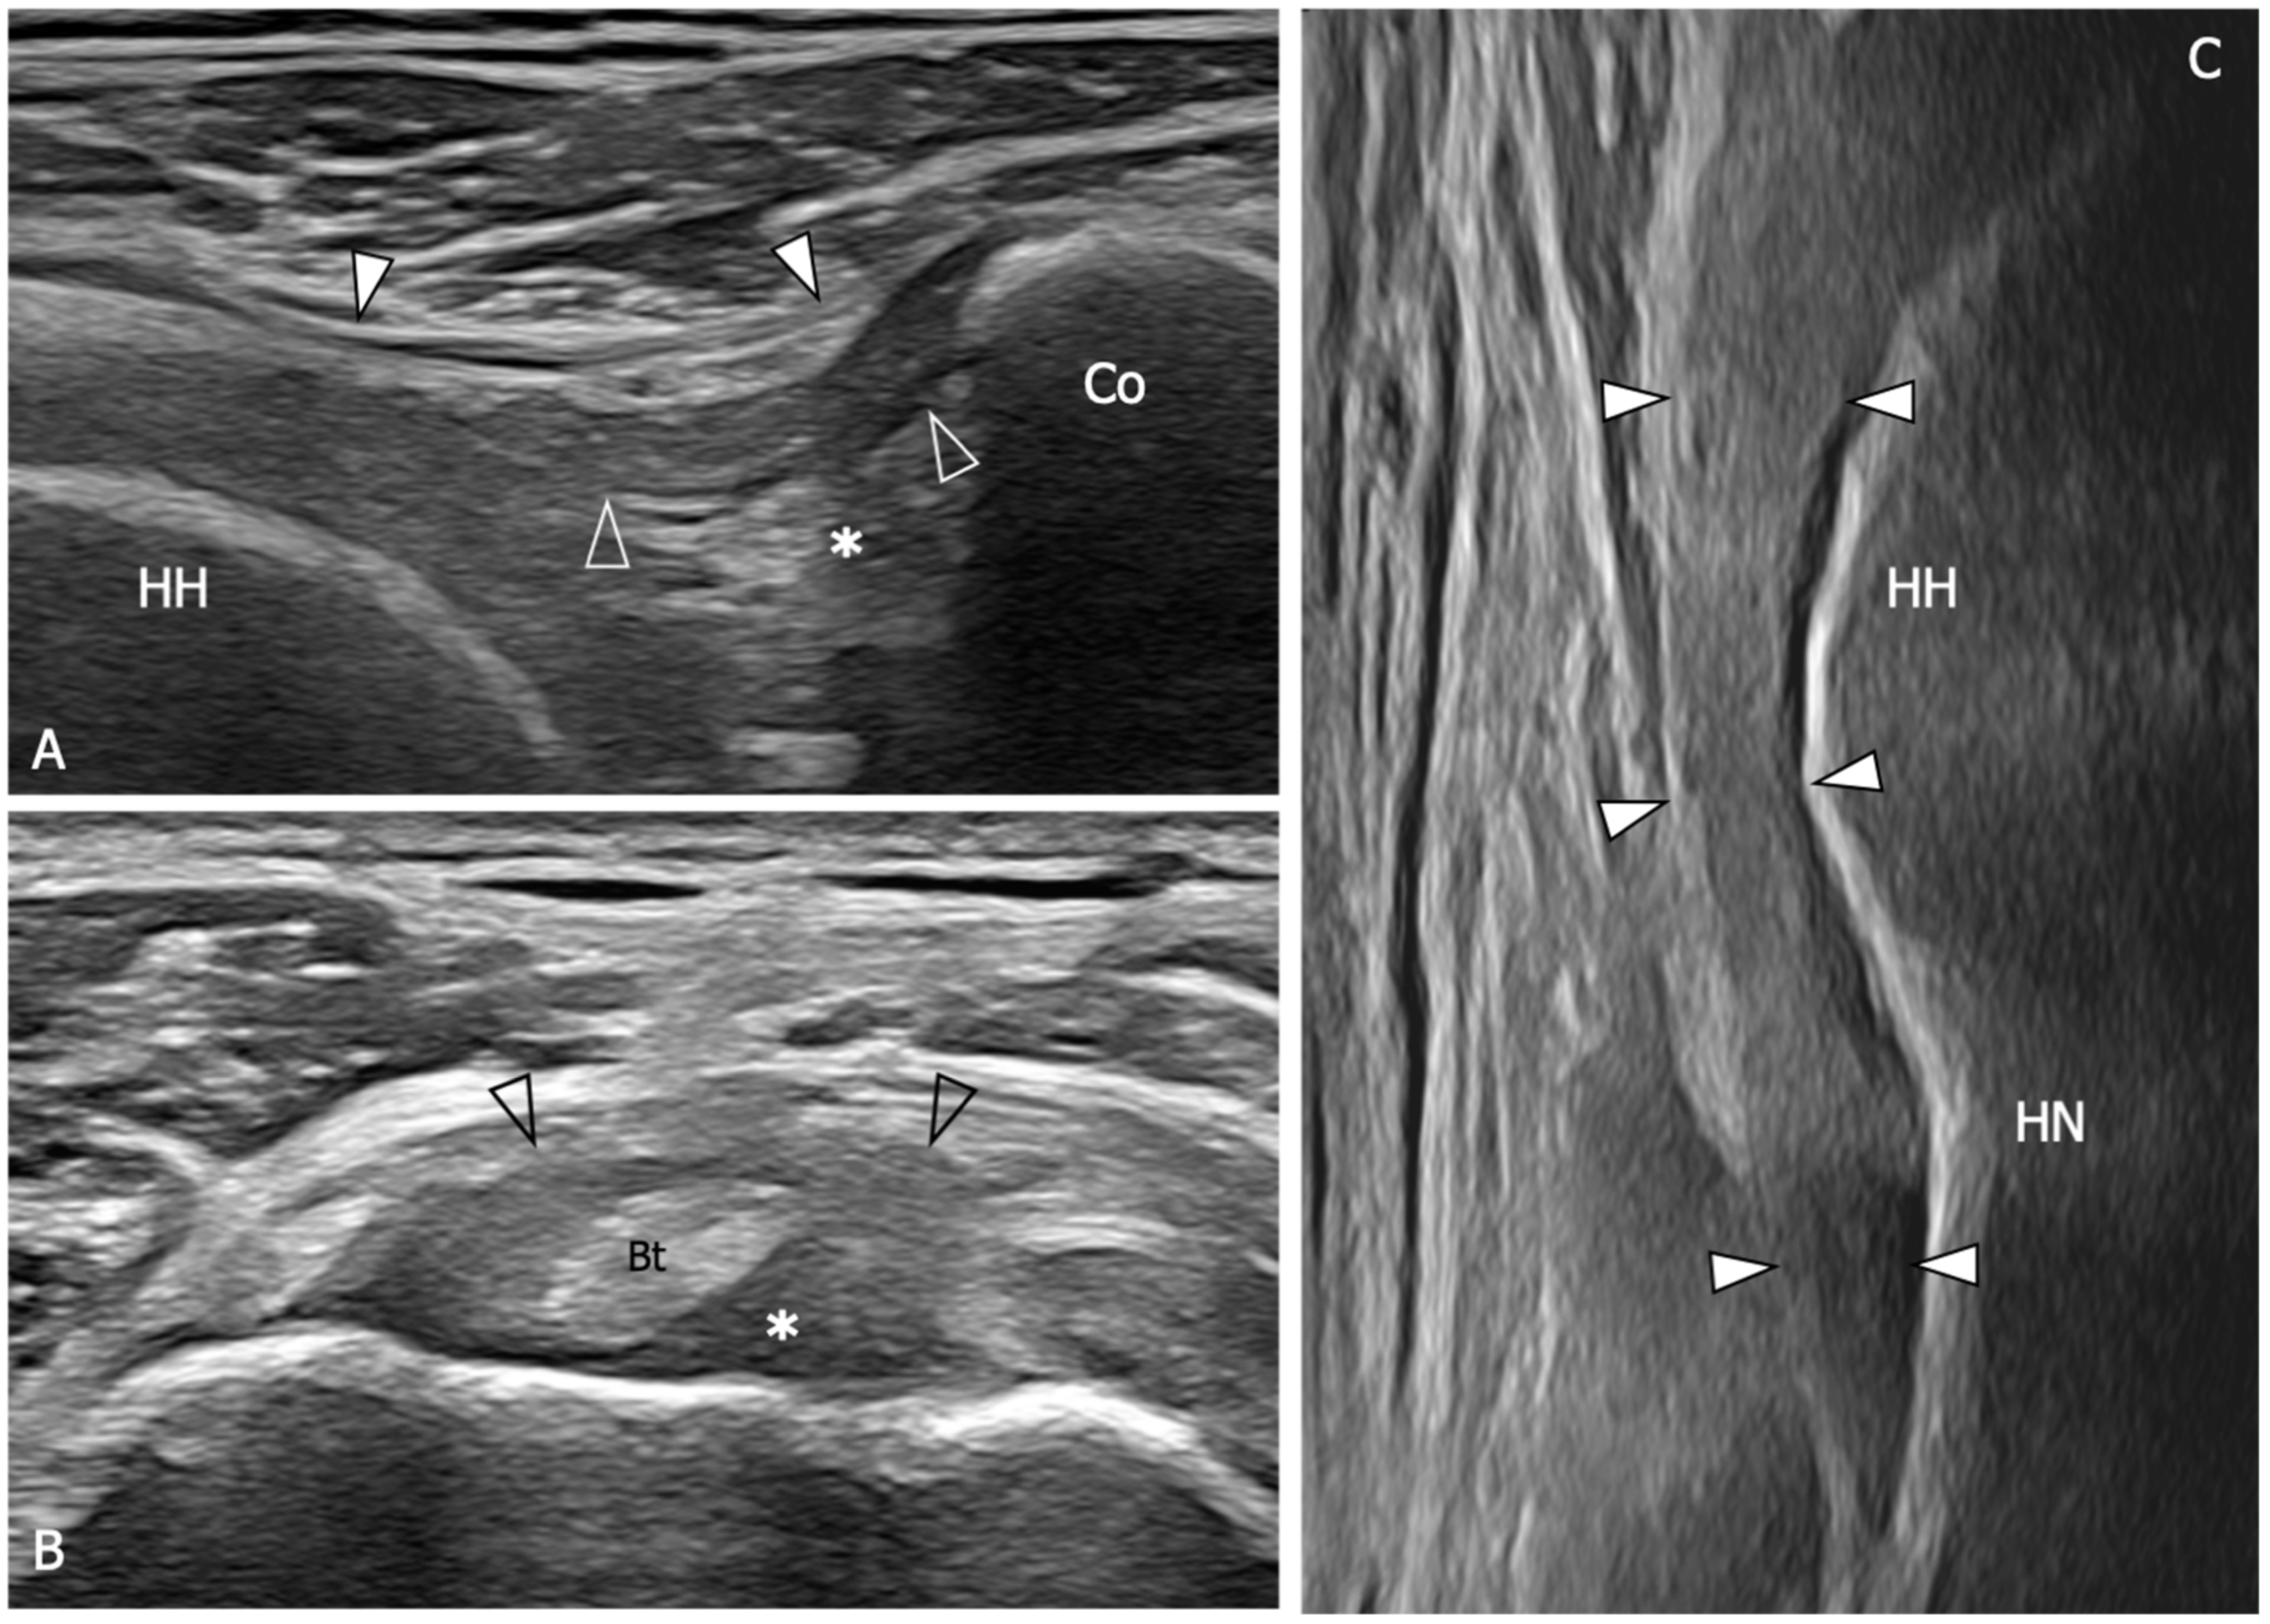

| An 88% sensitivity (95%CI: 74–95) and a 96% specificity (95%CI: 88–99) are demonstrated when US detect inferior capsule and coracohumeral thickening, rotator interval abnormality, and restricted range of motion. | [10] |

| The average CHL thickness measure both in short and long axis was 3 mm in shoulders affected by AC. Painful shoulders without AC diagnosis exhibited an average coracohumeral ligament thickness of 1.39 mm; asymptomatic shoulders had an average coracohumeral ligament thickness of 1.34 mm. | [64] |

| Patients with AC exhibited a significantly thicker coracohumeral ligament (1.2 mm) compared to both subjects with painful shoulders (0.54 mm) and healthy volunteers (0.4 mm). | [65] |